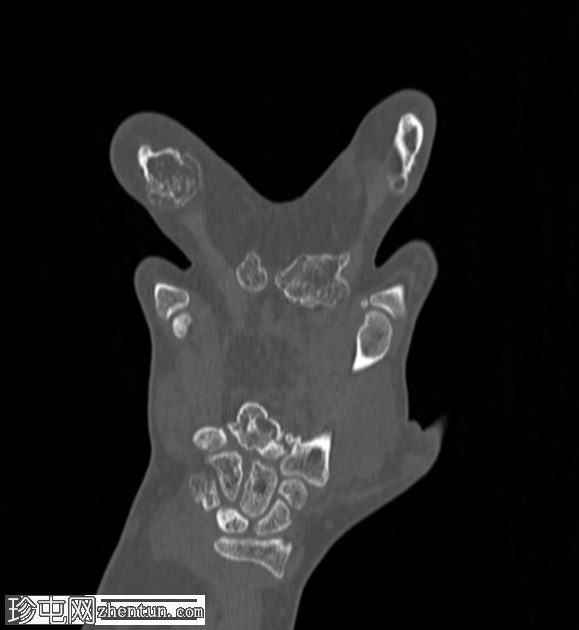

无名指和中指明显增大。患者掌骨和指骨骨质增生肥大,并伴有周围皮下脂肪过度增生。

骨窗

CT 扫描显示骨质过度生长和肥大、皮下脂肪过度生长以及神经纤维脂肪瘤性错构瘤。